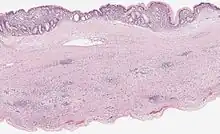

| Mucinous cystadenoma of the pancreas 6 |